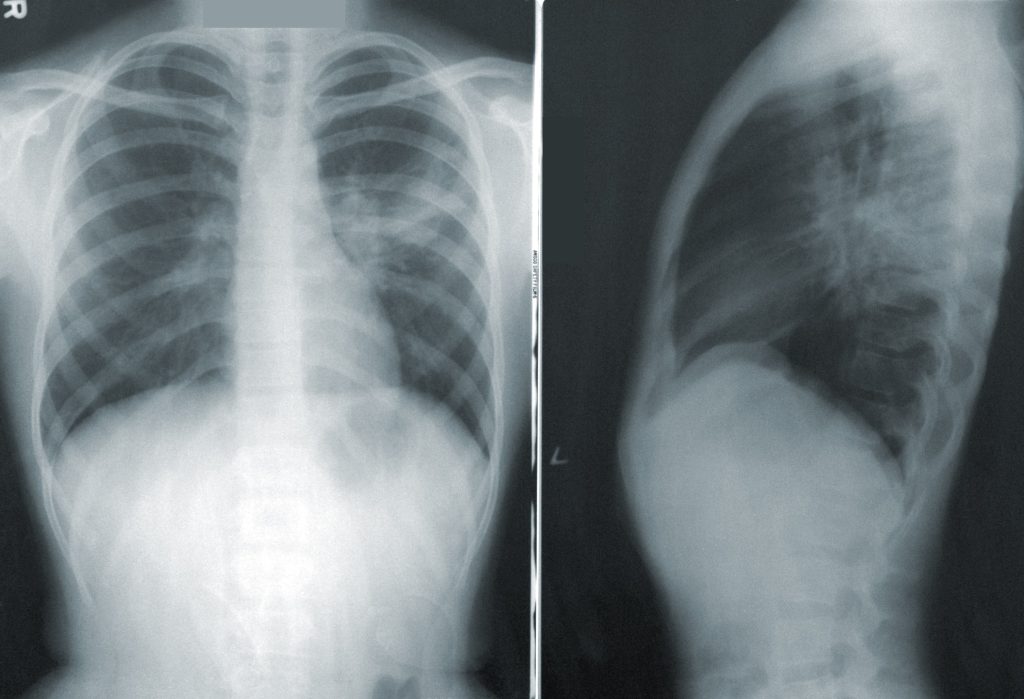

El padecimiento afecta al tejido que rodea a los alvéolos pulmonares, el cual se vuelve grueso y rígido, provocando una cicatrización permanente denominada fibrosis, que dificulta progresivamente la respiración.

Además, se disminuye la cantidad de oxígeno que los principales órganos del cuerpo deben recibir y los pacientes afectados manifiestan dolor torácico, fatiga, tos persistente, entre otros síntomas que impactan su calidad de vida y bienestar emocional.